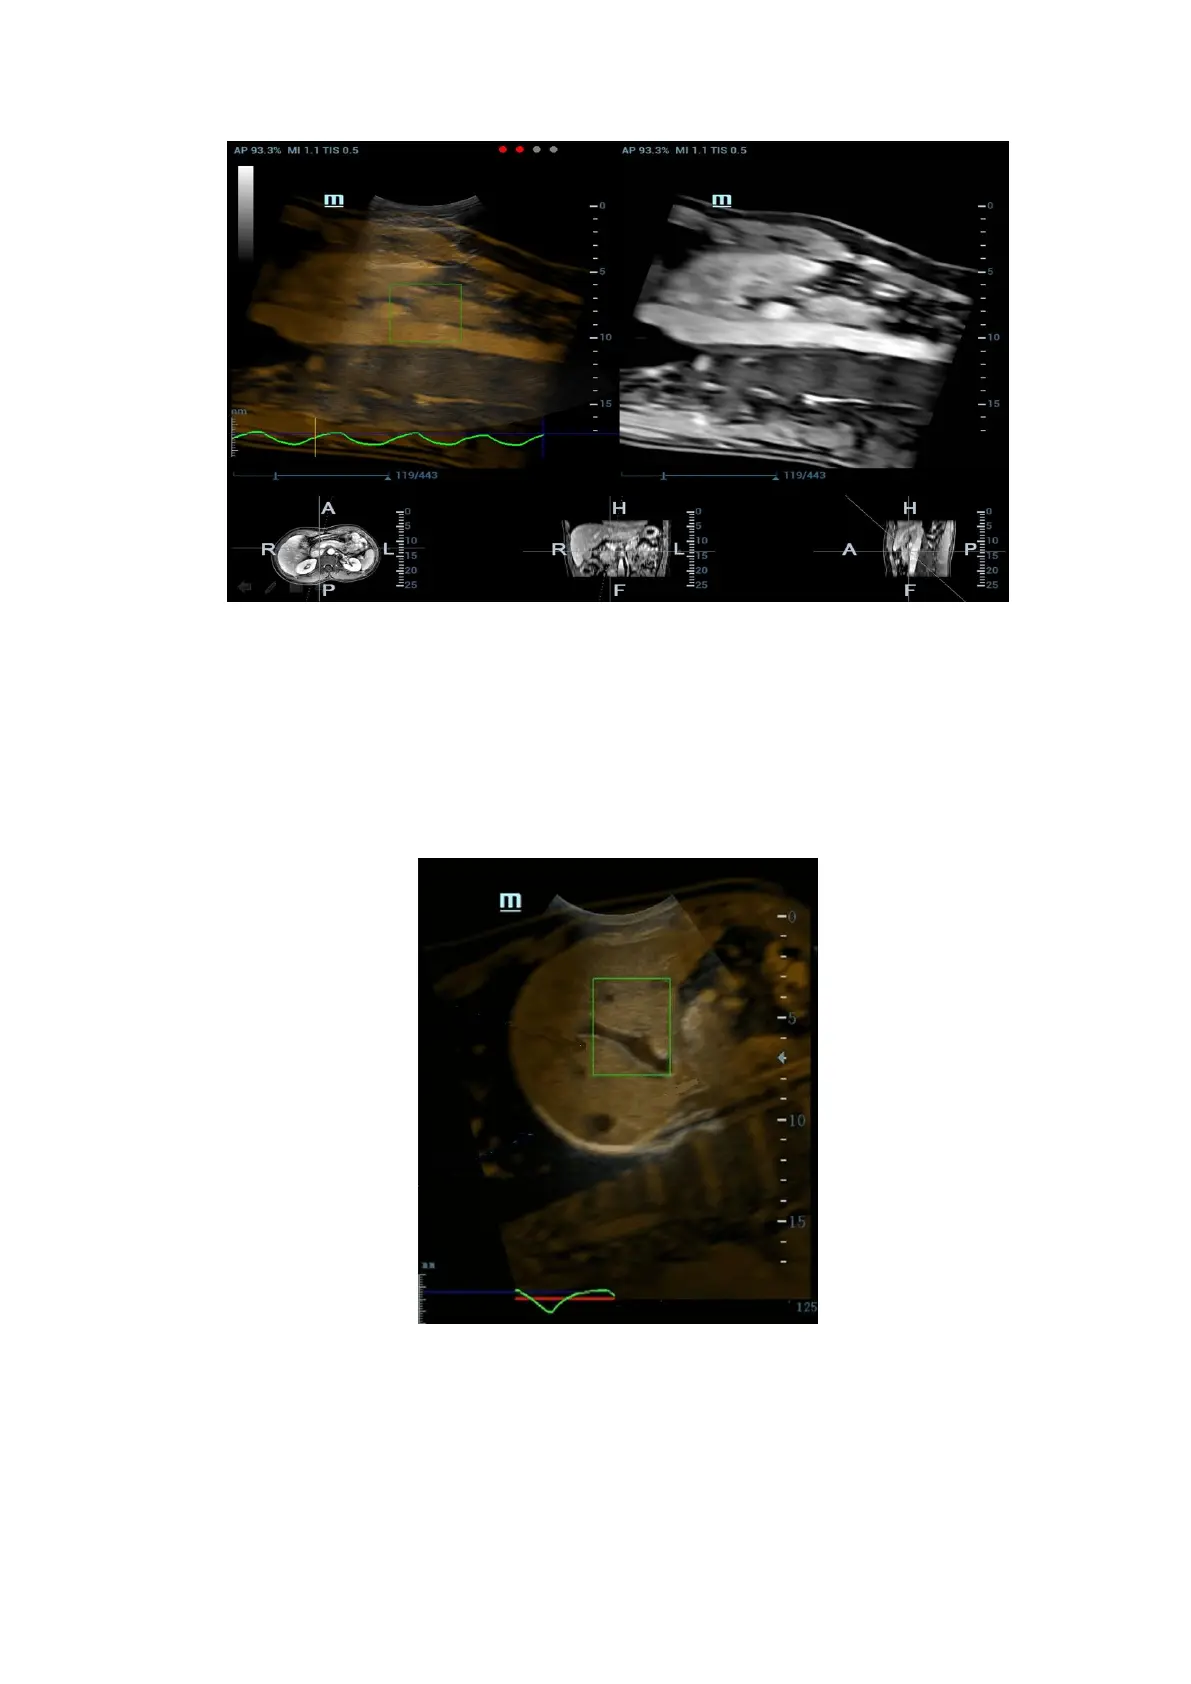

4. Tap [Motion Modeling]. If modelling succeeds, the system will play the cineloop automatically,

and ROI moves along with the motion of the respiration curve.

5. Tap [Motion Compen] to activate it. Move the probe. The Ultrasound System shows the CT

image which is processed by respiration compensation (Fusion Imaging with the respiration

compensation).

Respiration Range

The aspiration curve appears due to the active respiration depth. The respiration

curve beyond the scale becomes the straight line.